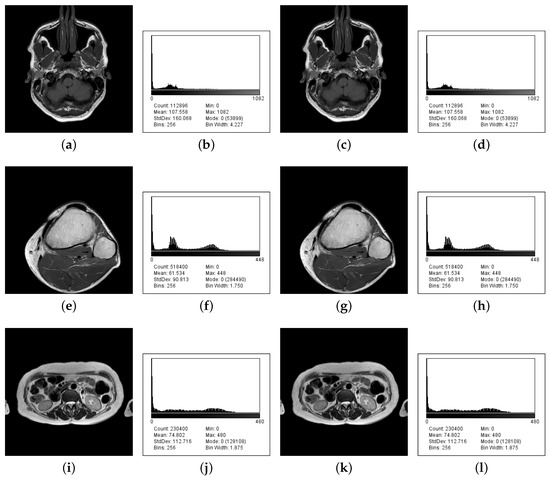

| Input Image | Image Size | Maximum Payload | Percent Volume | Available Levels | Input Levels | Message (Bytes) | MSE | PSNR (dB) |

|---|---|---|---|---|---|---|---|---|

| Brain IM_0001 | 336 × 336 | 83,179 | 73.68 | 1083 | 1050 | 0.0191 | 113.5238 | |

| Brain IM_0002 | 336 × 336 | 83,362 | 73.84 | 851 | 1050 | 0.0192 | 113.4977 | |

| Brain IM_0003 | 336 × 336 | 83,557 | 74.01 | 823 | 1050 | 0.0191 | 113.5218 | |

| Brain IM_0004 | 336 × 336 | 83,341 | 73.82 | 875 | 1050 | 0.0190 | 113.5319 | |

| Brain IM_0005 | 336 × 336 | 83,883 | 74.30 | 834 | 1050 | 0.0191 | 113.5198 | |

| Knee IM_0001 | 720 × 720 | 249,148 | 48.06 | 449 | 1042 | 0.0041 | 120.1618 | |

| Knee IM_0002 | 720 × 720 | 250,531 | 48.33 | 426 | 1042 | 0.0043 | 120.0302 | |

| Knee IM_0003 | 720 × 720 | 251,867 | 48.59 | 461 | 1042 | 0.0043 | 120.0263 | |

| Knee IM_0004 | 720 × 720 | 256,834 | 48.54 | 453 | 1042 | 0.0042 | 120.0637 | |

| Knee IM_0005 | 720 × 720 | 260,969 | 50.34 | 444 | 1042 | 0.0042 | 120.0558 | |

| Liver IM_0001 | 480 × 480 | 109,631 | 47.58 | 481 | 1119 | 0.0098 | 116.4055 | |

| Liver IM_0002 | 480 × 480 | 112,992 | 49.04 | 581 | 1119 | 0.0100 | 116.3465 | |

| Liver IM_0003 | 480 × 480 | 114,107 | 49.53 | 626 | 1119 | 0.0103 | 116.2160 | |

| Liver IM_0004 | 480 × 480 | 115,670 | 50.20 | 643 | 1119 | 0.0098 | 116.4325 | |

| Liver IM_0005 | 480 × 480 | 116,373 | 50.51 | 624 | 1119 | 0.0098 | 116.4383 |